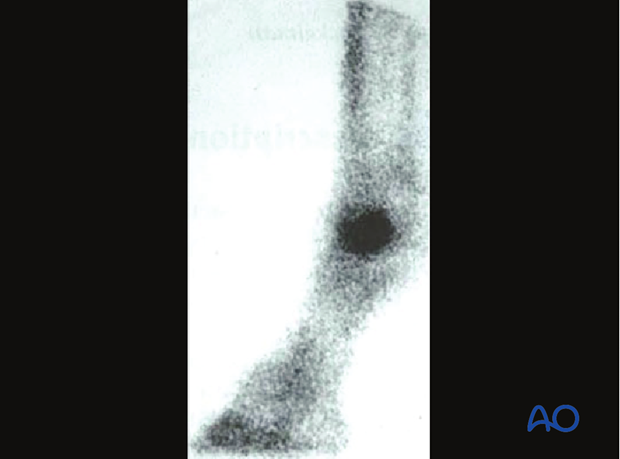

As with a number of other exercise induced fractures, condylar fractures appear to occur in stages. A common anamnesis includes: signs of repeated bouts of lameness associated with pain and swelling in the fetlock region; passive flexion of the metacarpophalangeal joint appearing painful; and, possible occasional point pain detectable in the distal metaphyseal region. These 2-3 day periods of lameness alternate with periods of apparent athletic soundness. Only after repeated radiographs are taken at different intervals and from various angles does the bony defect become visible [3]. There is scintigraphic evidence that there may be some predisposing (vascular) disorder of the distal metacarpus (see image) that precedes actual bony failure [4], as has been observed in humans [5, 6]. The gradual nature of the failure may be connected with prevailing loading characteristics, as has been demonstrated in experimental animals [7]. In describing the repair procedure below, the metacarpus will be used as an example. Mention will be made of any significant deviations applicable to the same fracture form